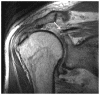

Anterosuperior glenoid impingement is a well documented cause of shoulder pain. It occurs when there is deep tearing of the subscapularis, with fibers becoming embedded between the anterosuperior glenoid and humeral head. To our knowledge, this has not been described in radiologic literature and we present MRI findings depicting this entity.